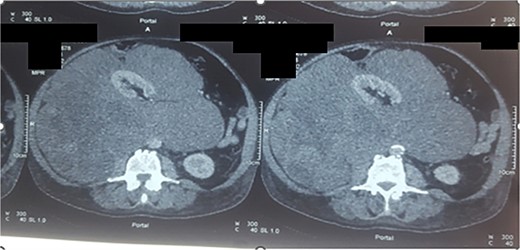

Preoperative staging, including computed tomography (CT) thorax, abdomen, and pelvis, showed no distant metastases. CT imaging (axial view, Fig. 1) identified a large retroperitoneal mass measuring 40 × 27 × 17 cm, involving the right kidney and its vasculature, displacing major structures like the inferior vena cava, duodenum, and pancreas. No magnetic resonance imaging (MRI) was performed.

Axial section of CT scan, parenchymal window showing a large retroperitoneal mass measuring 40 × 27 × 17 cm (liposarcoma).